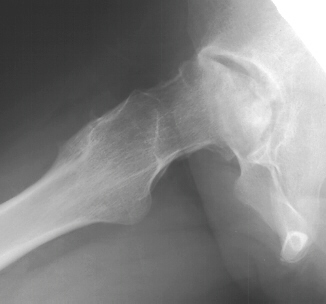

This treatment is expected to prevent further collapse of the

femoral head.

Four

years later, she is able to ambulate without any aids but complains

of a dull ache in her left hip and a limitation in rotation

.

Now at age eighteen, a total hip replacement is the best option

and she should do as well as others with chronic joint degeneration

should as rheumatoid arthritis.